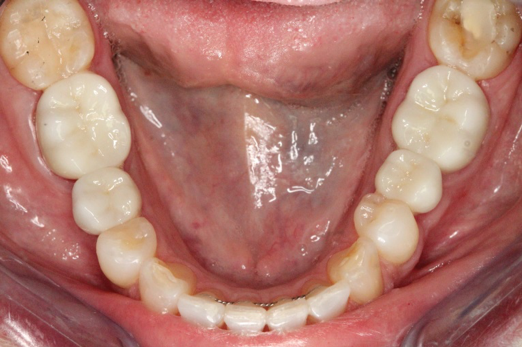

Fig 16. Final restorations (15 weeks postoperatively).

Figure 16

The final impression appointment follows the light-load phase, provided the implant is stable and the soft tissue is acceptable to the clinician. Polyvinyl putty and light-body impression materials were used in this case; analog casts and final full-zirconia full crowns were fabricated (Figure 16). The patient provided feedback that chewing was comfortable and without food impactions. Keratinized gingival cuff was developed, and natural-tooth contours for the restorations mimicked what is normally found in human dentition. The healed bone surrounding the ceramic dental implant was similar in density and crestal levels in comparison with the adjacent natural teeth, evident in the radiographic evaluation (Figure 17). Final long-term restorations at the gingival crest and restoration interfaces were also consistent in optimum periodontal health and gingival height. Arch-form integrity was upheld and occlusion was managed; osseointegration and light-load principles optimized the success of the restorations, and an acceptable, harmonious esthetic outcome was achieved for the patient.